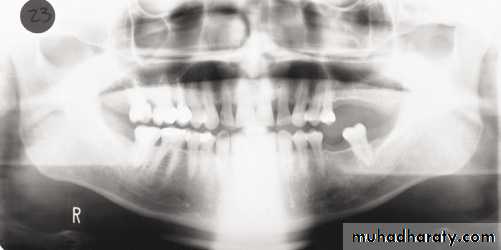

In a good panoramic radiograph:

The mandible is “U” shaped.

The condyles are positioned about equal distance from the inside edges of the image and 1⁄3 of the way down from the top edge of the image.

The occlusal plane exhibits a slight curve or “smile line,” upwards.

The roots of the maxillary and mandibular anterior teeth are readily visible with minimal distortion.

Magnification is equal on both sides of the midline.